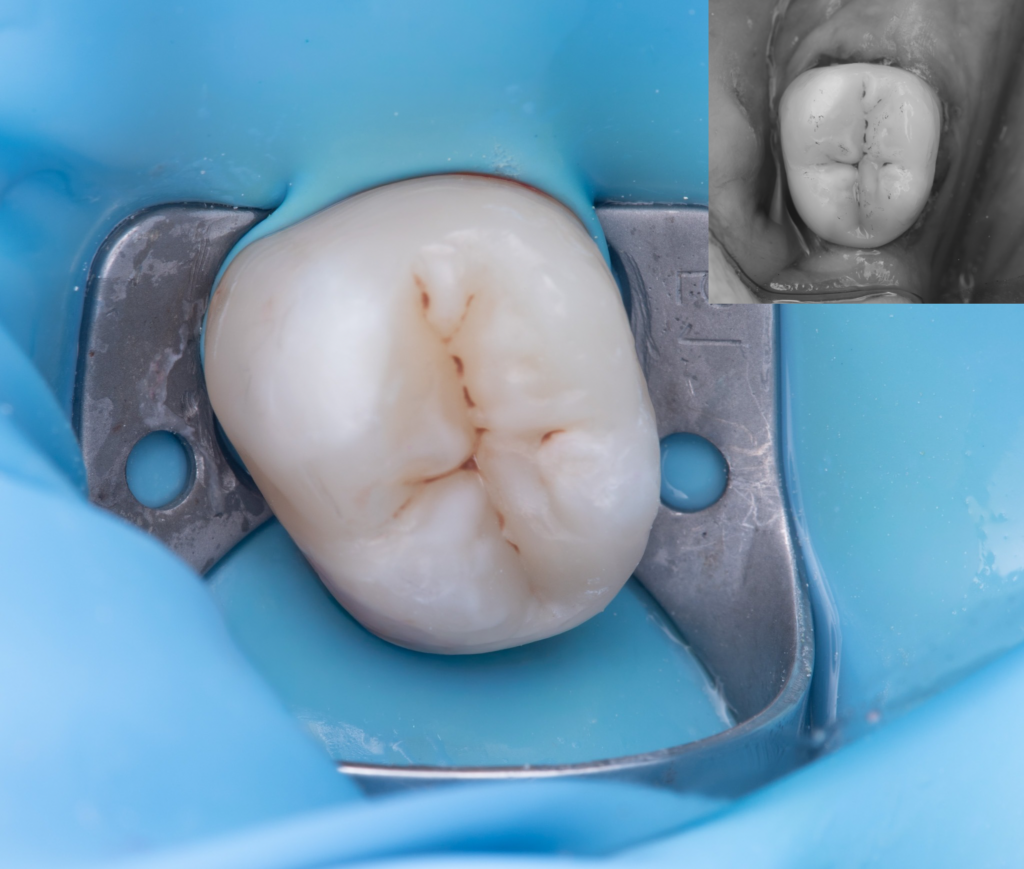

The following materials were used: Estelite Flow A3 / Asteria A3B / OcE, EverX Bulk Fill, and anatomical restoration was completed with NeoSpectra A3, with characterization using Enamel Brown and White stains.

Total treatment time: 1 hour 10 minutes.